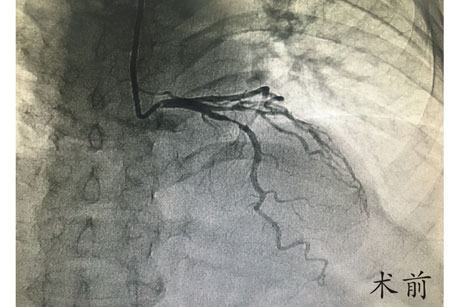

在赵慧强主任的指导下,心内科介入治疗团队选择创伤最小的桡动脉径路,应用常规穿刺器械及造影导管完成了对患者的冠脉造影检查,造影提示患者前降支近段90%节段性重度狭窄,根据患者病变情况,必须行冠脉介入治疗置入支架。经介入团队讨论后,决定即刻对患者进行前降支介入治疗,考虑患者体型小,主动脉窦部较窄,在没有专用指引导管的情况下,选用常规较小型号指引导管顺利到达左冠开口,随后应用常规导丝顺畅通过病变部位,球囊预扩张及支架置入先后顺利完成,全程仅耗时40分钟,手术取得圆满成功。